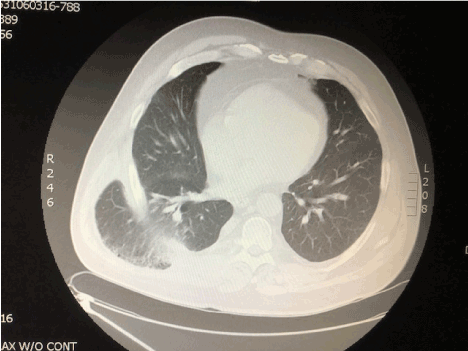

A chest x-ray showed an indistinct right basilar density with a potential small effusion possibly related to atelectasis or pneumonia (Figures 1A and 1B). There were no evident rib fractures.  While preparing for a chest CT, the patient coughed, and the bulge recurred.  CT images showed a large herniation of the right lower lobe between the 9th and 10th rib interspace. The adjacent ribs were separated with interruption of the associated intercostal muscles (Figures 2A and 2B, Figure 3 and Figure 4).

Figure 2B.  CT of chest, non-contrast, lung windows, axial view at similar level as Figure 2A.